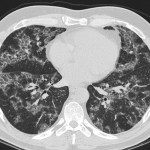

Crazy Paving on Chest CT

Crazy Paving is a appearance that is basically a linear network or reticular pattern in the crazy-paving...